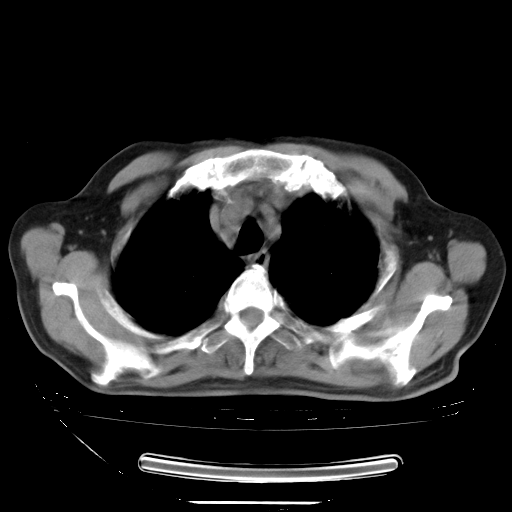

胸腹部CT,诊断意见:左上肺叶钙化灶、左侧胸膜局限性增厚并钙化、胆囊炎。描述部分肺组织呈磨玻璃样改变。